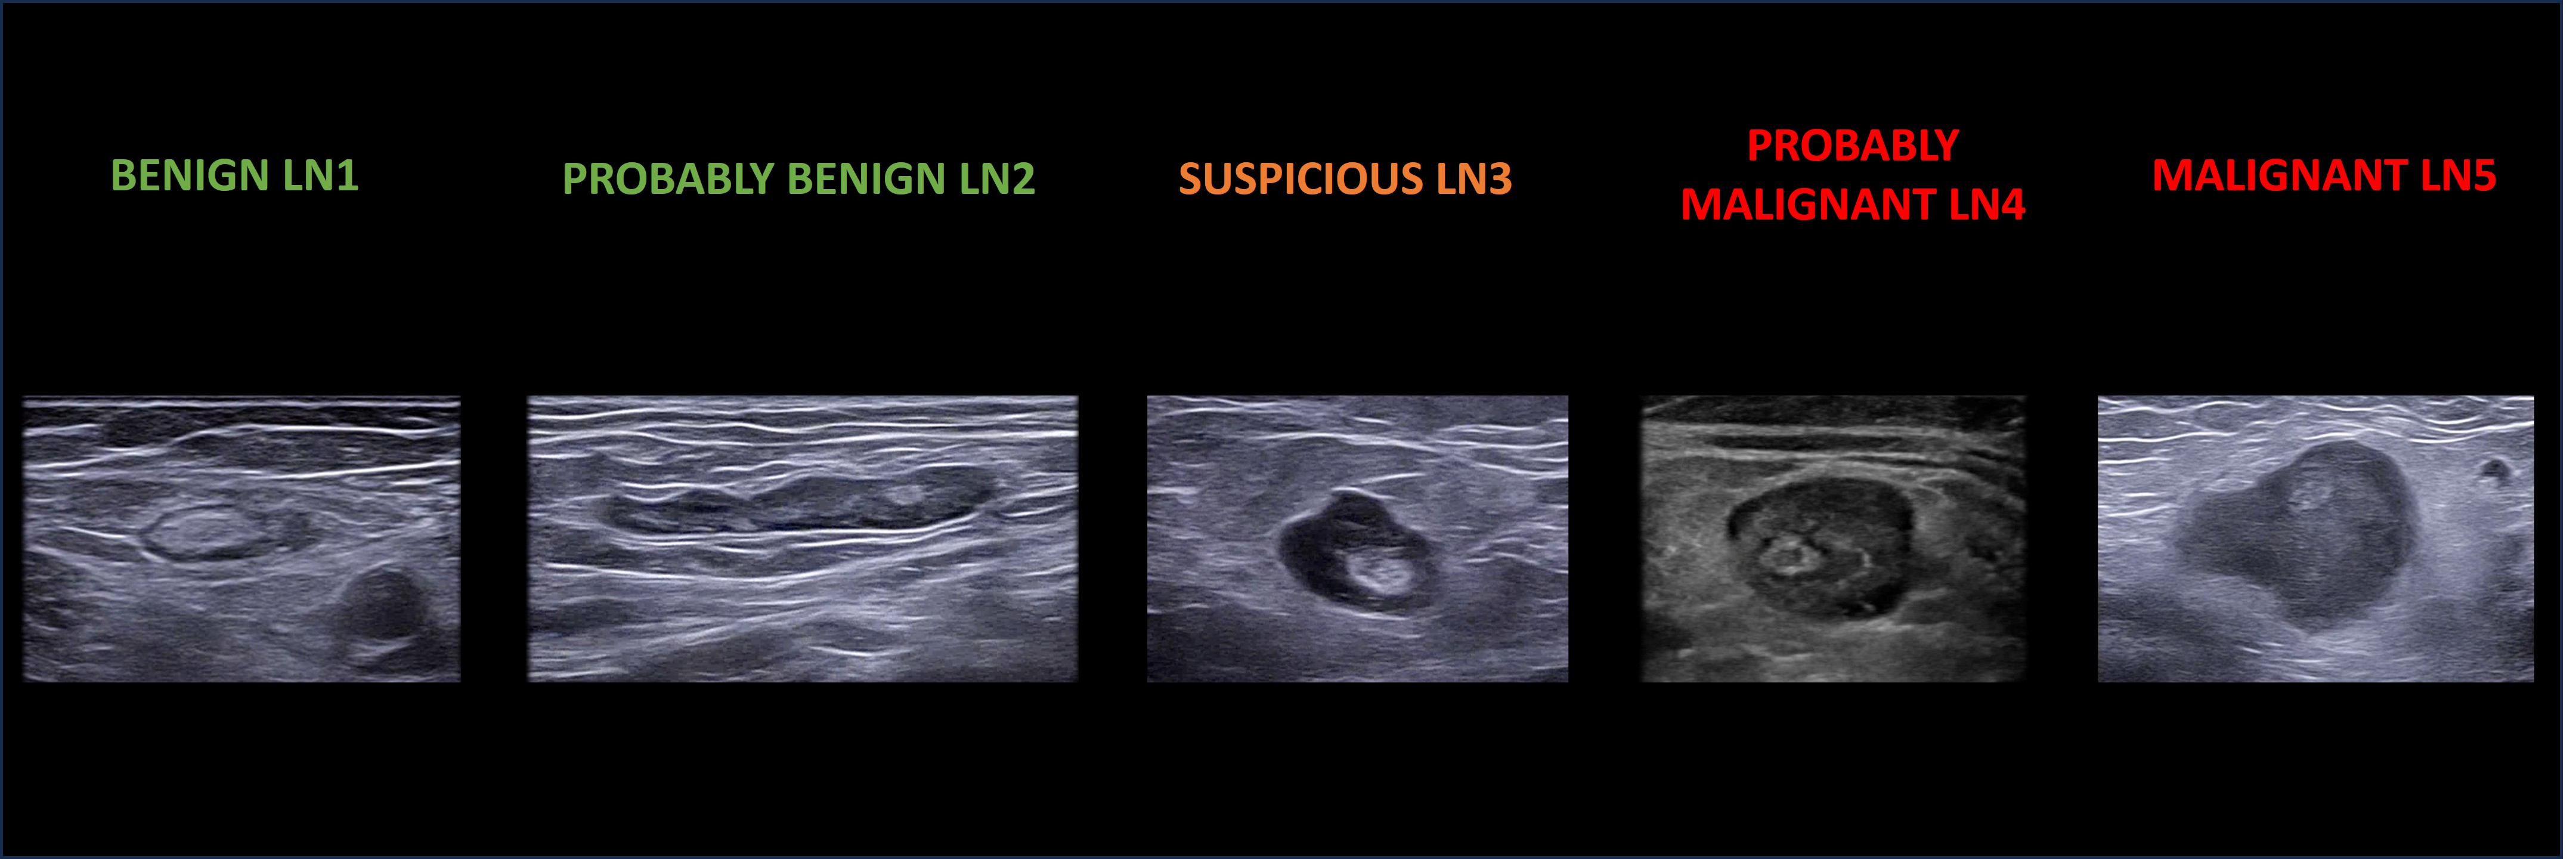

Final classification

A subjective assessment, based on the combined evaluation of dimensional, morphological and vascular characteristics, allows the operator to classify each lymph node from LN1 (normal) to LN5 (metastatic) (Figure 12).

12

Five categories (LN1–LN5) of lymph node classification by subjective assessment.

Examples of lymph node categories, characterized by their ultrasound features and the associated subjective evaluation, are presented below.

Normal. Oval shape, visible nodal-core sign, thin homogeneous cortex, hilar flow (LN1).

Reactive. Oval shape, visible nodal-core sign, concentrically thickened cortex due to immune response (LN2). Some may lack medulla/hilum (LN3).

Post-reactive. Large hyperechoic medulla, thin cortex, sometimes a ‘sandwich’ pattern (LN1).

Metastatic. Eccentric cortical thickening displacing hilum/medulla, non-homogeneous cortex (e.g. cystic areas), hypoechoic echogenicity relative to surrounding tissue, capsular interruption, or transcapsular vascular architecture. Fully infiltrated nodes are round and lack hilum/medulla (LN4–5).